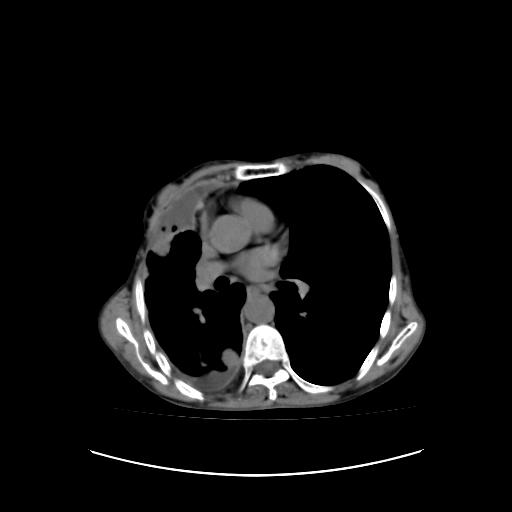

标题: CT16930:女 59 胸痛6个月 胸水脱落细胞学见瘤细胞 [打印本页]

标题: CT16930:女 59 胸痛6个月 胸水脱落细胞学见瘤细胞

可见多发肺内病灶,且胸膜病灶较多有圆球状而非丘状,多考虑胸膜转移瘤伴胸腔积液,右侧胸廓缩小固定,且部分病灶呈丘状,尚不除外恶性胸膜间皮瘤伴肺内转移

右侧胸膜增厚,局部呈结节状增厚,右侧胸腔少量积液。双肺未见确切肿块影。纵隔未见淋巴结肿大。气管、支气管通畅。考虑右侧胸膜间皮瘤(恶性?)可能性大。不除外癌性胸膜炎。

恶性胸膜间皮瘤伴肺内转移可能性大;或胸膜、肺内均为转移瘤,左肺下叶亦见多发小结节影。

右侧胸廓塌陷,右侧胸膜广泛增厚并见多发胸膜结节,右侧少量胸腔积液并包裹。

右侧广泛胸膜增厚,局部呈结节状增厚,右侧胸腔少量积液。双肺未见确切肿块影。纵隔未见淋巴结肿大。气管、支气管通畅。考虑右侧胸膜间皮瘤(恶性?)可能性大。支持!

右侧胸膜转移瘤,原发灶可能就在在右肺,另外建议检查右侧乳腺.

右胸腔结节均考虑来自胸膜(部分来源于叶裂),考虑胸膜间皮瘤或转移瘤.